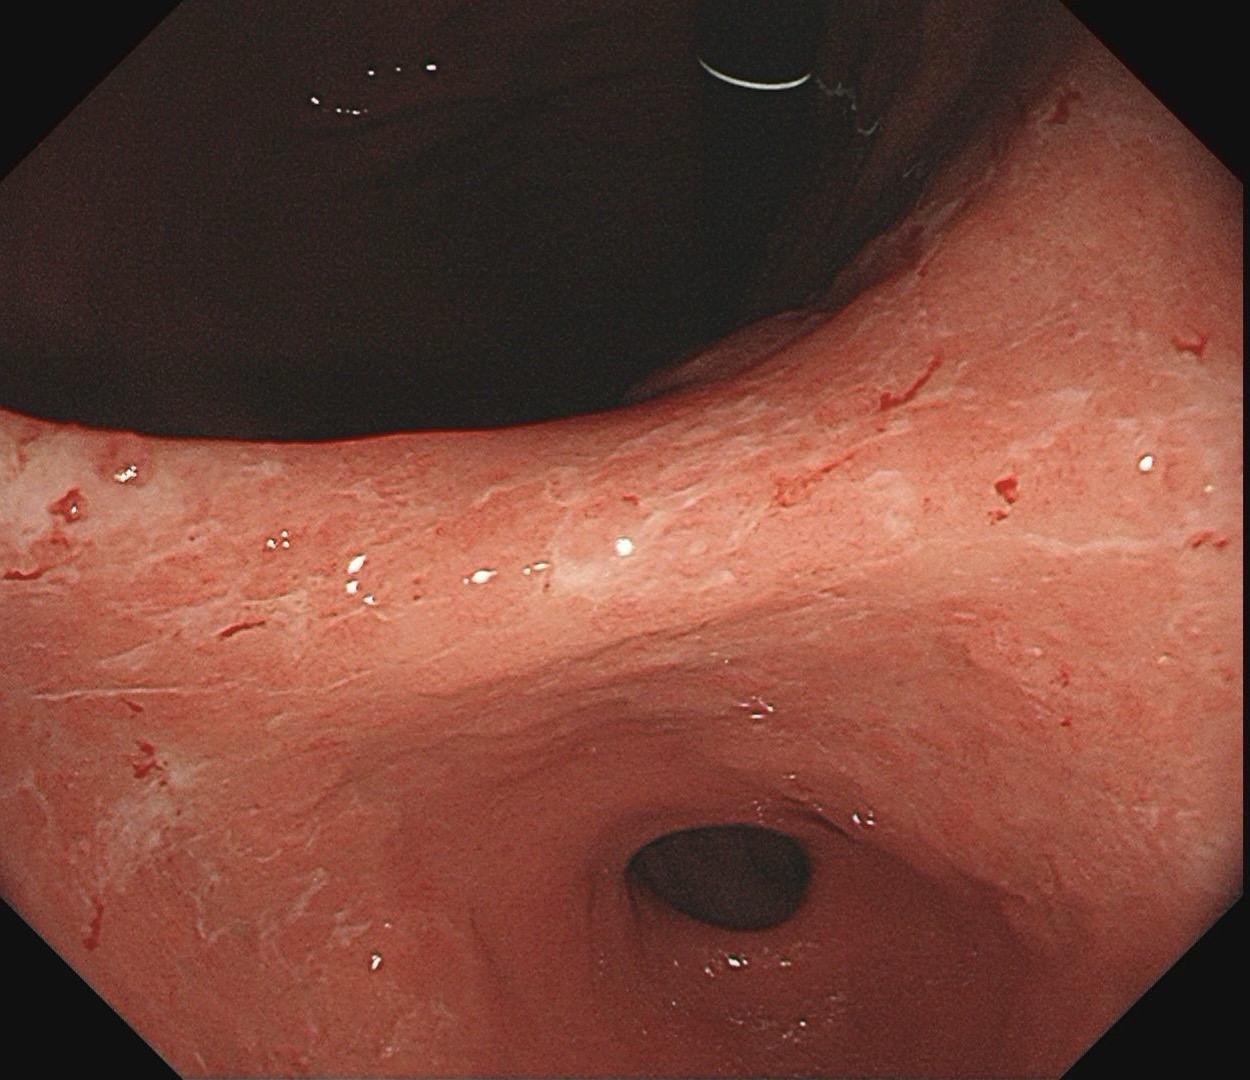

男,61岁,胃巨大褪色调病变。答案在最后一张图片,你猜对了吗? 患者因上腹部饱胀行胃镜检查,Hp阴性背景,胃窦至贲门下见一巨大褪色调病变,边界清晰,病变相对表浅,未见明显溃疡及隆起,胃壁较柔软,充气顺应性佳,予多点活检确诊,拟外科手术行全胃切除。做这么多年胃镜,还是第一次遇到这样的……